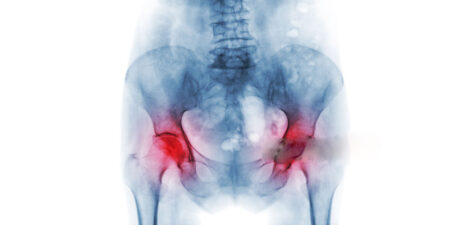

Entzündungsprozesse spielen eine zentrale Rolle bei vielen muskuloskelettalen Erkrankungen. Die extrakorporale Stoßwellentherapie (ESWT) hat sich als eine effektive Methode zur Schmerzreduktion und Entzündungshemmung erwiesen, indem sie über das Nervensystem auf den neurogenen Entzündungskreislauf einwirkt. Ihre direkten Effekte auf die biochemischen Entzündungsmechanismen in Zellen und Gewebe sind vorhanden, wenn auch begrenzt. Hier kann die Kombination mit phytopharmazeutischen Wirkstoffen wie Curcumin, Boswellia, Bromelain und Anthocyanen einen synergistischen Effekt erzielen, indem sie gezielt gewebespezifische, intrazelluläre Entzündungsprozesse modulieren.